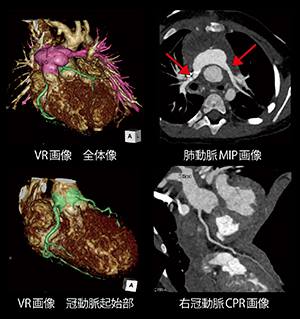

心電図同期Sequenceモードによる小児心臓2beat撮影

南 汐里(金沢医科大学病院医療技術部診療放射線技術部門)

【背 景】1歳1か月,体重10kgの女児。出生時,動脈管開存を伴うⅡ型の完全大血管転位症と診断された。根治術として,冠動脈を肺動脈に移植し大動脈と肺動脈を入れ替えるジャテン術,心房・心室中隔欠損閉鎖術が行われた。術後経過観察にて肺動脈狭窄を認め,バルーン拡張術を施行するもあまり改善されず,外科的肺動脈形成術が施行された。移植した冠動脈の評価および肺動脈狭窄改善評価の目的で造影CTが依頼された。

【所 見】ジャテン術後,肺動脈は大動脈の前方で再建されている。また,両側肺動脈の拡張を認めた。冠動脈走行は明瞭に確認でき,術前と比較して明らかな狭窄は認められない。右肺動脈起始部径8.6mm(形成術前5.3mm),左肺動脈起始部径6.0mm(形成術前3.4mm)。

【訴求ポイント】(1) 心電図同期を用いた2beat撮影にて冠動脈を描出:小児は放射線感受性が高いため,被ばく線量を抑えられるTurbo Flash Spiral撮影を第一選択としていたが,本症例では冠動脈評価が必要であったためProspectiveモードであるSequence撮影を用いた。SOMATOM Forceのディテクタ幅は約6cmであるため,心臓全体をカバーできる2beatで撮影。被ばく線量低減のためにPulsingをManualで収縮期(100〜230ms)のみ曝射されるよう設定した。また,CARE kVをonにして70kVの低管電圧を使用することで,さらなる被ばく低減を図った。(2) 造影剤の減量:希釈造影剤を用い,低管電圧70kVを使用。CARE Bolusトリガー後すぐに生理食塩水の後押しに切り替えることで,投与量を8mL(240mgI/kg)に抑えることができた。これらの工夫により,高心拍な小児心臓でも冠動脈評価を可能とし,低被ばくおよび少量造影剤で診断に有用な3D画像を提供することができた。